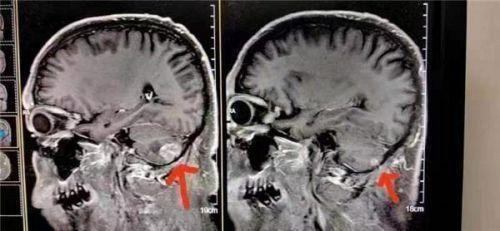

案例6、肺小细胞肺癌脑转移

患者在北京301医院检查治疗结果左脑肿瘤大于右脑肿瘤,陈海林采取采取纯中药的临床治疗,经三个月的治疗,于2023年6月28日的颅脑磁共振平扫十增强:1:右侧小脑转移瘤复查与2o23年3月9日MR片对比,病变基本消失。这个结果连301医院的都声称是奇迹。Case 24: Small cell lung cancer with brain metastasis

The patient underwent examination and treatment at Beijing 301 Hospital, and the results showed that the left brain tumor was larger than the right brain tumor. Chen Hailin adopted clinical treatment with pure Chinese medicine, and after three months of treatment, on June 28, 2023, the brain magnetic resonance plain scan with ten contrasts: 1. Compared with the MR film on March 9, 2023, the right cerebellar metastatic tumor reexamined and the lesion basically disappeared. This result is even claimed to be a miracle by Hospital 301.